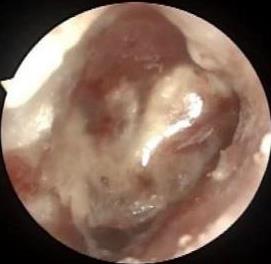

• 利那洛肽联合西甲硅油与复方聚乙二醇电解质散对便秘患者肠道清洁效果的影响

2025, 31(6):44-53. DOI: 10.12235/E20240604

摘要:目的 探讨利那洛肽联合西甲硅油与复方聚乙二醇电解质散(PEG)对便秘患者肠道清洁效果的有效性和安全性。方法 采用前瞻性随机对照试验,通过单盲法,纳入2023年4月-2024年8月于该院消化内镜中心行结肠镜检查的便秘患者383例,随机分为常规组(128例)、实验A组(128例)和实验B组(127例)。常规组采用3 L PEG(Ⅰ)溶液,实验A组采用290 μg利那洛肽 + 2 L PEG溶液,实验B组采用290 μg利那洛肽 + 30 mL西甲硅油+2 L PEG溶液。比较3组患者的肠道准备效果[Boston肠道准备量表(BBPS)评分和去泡效果]、病变检出率、首次排便间隔时间、排便次数、盲肠插管成功率、进镜时间、退镜时间、不良反应发生率和重复检查意愿等。结果 3组患者BBPS评分比较,差异无统计学意义(P > 0.05);实验B组的去泡效果评分明显低于常规组和实验A组,差异均有统计学意义(P < 0.05);实验B组的病变总检出率和息肉检出率明显高于常规组和实验A组,差异均有统计学意义(P < 0.05);常规组的首次排便间隔时间明显长于实验A组和实验B组,差异均有统计学意义(P < 0.05);3组患者排便次数比较,差异无统计学意义(P > 0.05);3组患者盲肠插管成功率均为100.0%,进镜时间相当,差异均无统计学意义(P > 0.05);实验B组的退镜时间明显短于常规组和实验A组,差异均有统计学意义(P < 0.05);常规组腹胀腹痛发生率和不良反应总发生率明显高于实验A组和实验B组,差异均有统计学意义(P < 0.05);常规组重复检查意愿率明显低于实验A组和实验B组,差异均有统计学意义(P < 0.05)。结论 290 μg利那洛肽联合30 mL西甲硅油与2 L PEG溶液方案在便秘患者肠道准备上具有优势,较3 L PEG溶液和290 μg利那洛肽+2 L PEG溶液方案,可获得更好的肠道清洁效果,且安全性和患者重复检查意愿率高,可作为便秘患者肠道准备的推荐方案。